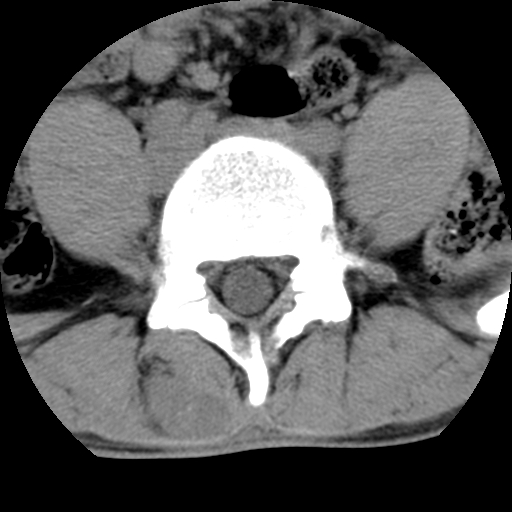

男,腰背痛

本人诊断1tb2包虫,请会诊

1)右侧竖脊肌稍低密度肿块伴钙化(性质待定),不排除肿瘤可能;建议行进一步检查。2)腰椎间盘突出。

1.右侧竖脊肌软组织肿块伴团块状钙化,首先考虑血管瘤可能性大;建议行进一步检查;2。腰椎间盘突出。